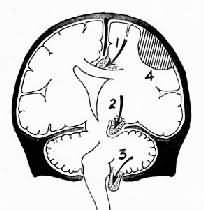

升高的颅内压可引起脑移位、脑室变形、使部分脑组织嵌入颅脑内的分隔(大脑镰,小脑天幕)和颅骨孔道(如枕骨大孔等)导致脑疝形成(herniation)。常见的脑疝有以下类型。

1.扣带回疝又称大脑镰下疝,是因一侧大脑半球特别是额、顶、颞叶的血肿或肿等占位性病变,引起中线向对侧移位,同侧扣带回从大脑镰的游离边缘向对侧膨出,形成扣带回疝。疝出的扣带回背侧受大脑镰边缘压迫形成压迹,受压处的脑组织发生出血或坏死。此外,大脑前动脉的胼胝体支也可受压引起相应脑组织梗死。大脑冠状切面上可见对侧的侧脑室抬高,第三脑室变形,状如新月(图16-6)。

脑疝模式图

图16-6 脑疝模式图

1.扣带回疝;2.海马钩回疝;3.小脑扁桃体疝;4.硬膜外血肿

2.小脑天幕疝又称海马钩回疝。位于小脑天幕以上的额叶或颞叶内侧的肿出血、梗死等病变引起脑组织体积肿大,导致颞叶的海马钩回经小脑天幕孔向下膨出。海马钩回疝可导致以下后果:①同侧动眼神经在穿过小脑天幕裂孔处受压,引起同侧瞳孔一过性缩小,继之散大固定,及同侧眼上视和内视障碍。②中脑及脑干受压后移,可导致意识丧失;导水管变狭,脑脊液循环受阻加剧颅内压的升高;血管牵伸过度,引起中脑和桥脑上部出血梗死,可导致昏迷死亡。③中脑侧移,使对侧中脑的大脑脚抵压于该侧小脑天幕锐利的游离缘上,形成Kernohan切迹。严重时该处脑组织(含锥体索)出血坏死,导致与天幕上原发病变同侧的肢体瘫痪,引起假定位症。④压迫大脑后动脉引起同侧枕叶距状裂脑组织出血性梗死(图16-7)。